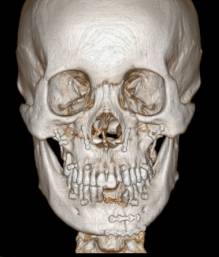

正 畸-正颌联合治疗矫治不对称牙颌面畸形

目前可使用软件将螺旋CT或锥束CT等影像学数据经计算机处理后,三维重建患者的颌骨形态,辅助牙颌面畸形的诊断,模拟手术截骨、移动、固定等,并制作相应的数字化导板辅助术中手术实施。同时因为计算机辅助手术设计可以更为直观的视察到术后颌骨的位置,更方便患者直观的了解手术效果,理解手术方案,便于医患沟通交流。

(摘自“第四章第三节 牙颌面畸形治疗计划”)

计算机辅助正颌外科手术设计